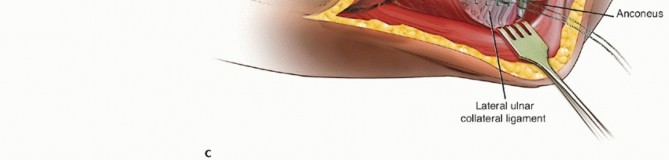

The lateral ulnar collateral ligament is an important stabilizer against varus and posterolateral rotational instability of the elbow37 and should be preserved or repaired after radial head arthroplasty (FIG 1).

FIG 1 • The ligaments on the lateral aspect of the elbow include the lateral ulnar collateral ligament, the radial collateral ligament, and the annular ligament. The lateral ulnar collateral ligament is an important stabilizer against varus and posterolateral rotational instability of the elbow and should be preserved or repaired after radial head arthroplasty.*

Dissection should stay anterior to the lateral ulnar collateral ligament to prevent the development of posterolateral rotatory instability (see FIG 1).